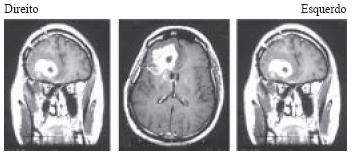

As imagens de RNM, com seqüências ponderadas em T1, feitas com contraste gadolíneo, mostram a presença de um processo expansivo na região frontal direita.

O achado anátomo- patológico mais relacionado à piora do prognóstico do tumor apresentado é